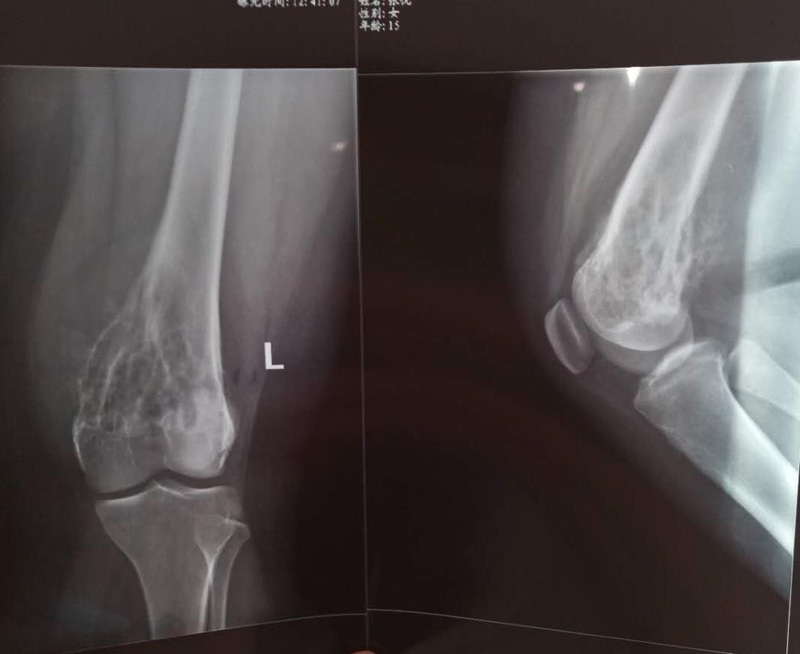

骨肉瘤手术手术前

患者张某,女,14岁,诊断为“左股骨远端骨肉瘤”,当地医院因为医疗技术和能力的限制,只能考虑截肢手术。患者家属通过平台推荐,指定到哈尔滨医科大学附属第二医院骨关节科找到陶树清主任就诊。经过严密、悉心的诊断,对小女孩还进行了“瘤段切除、肿瘤假体置换”手术,保留了小女孩肢体的健全,同时使她能够正常行走。

携生医疗骨肉瘤手术前X光片

骨肉瘤手术前X光片